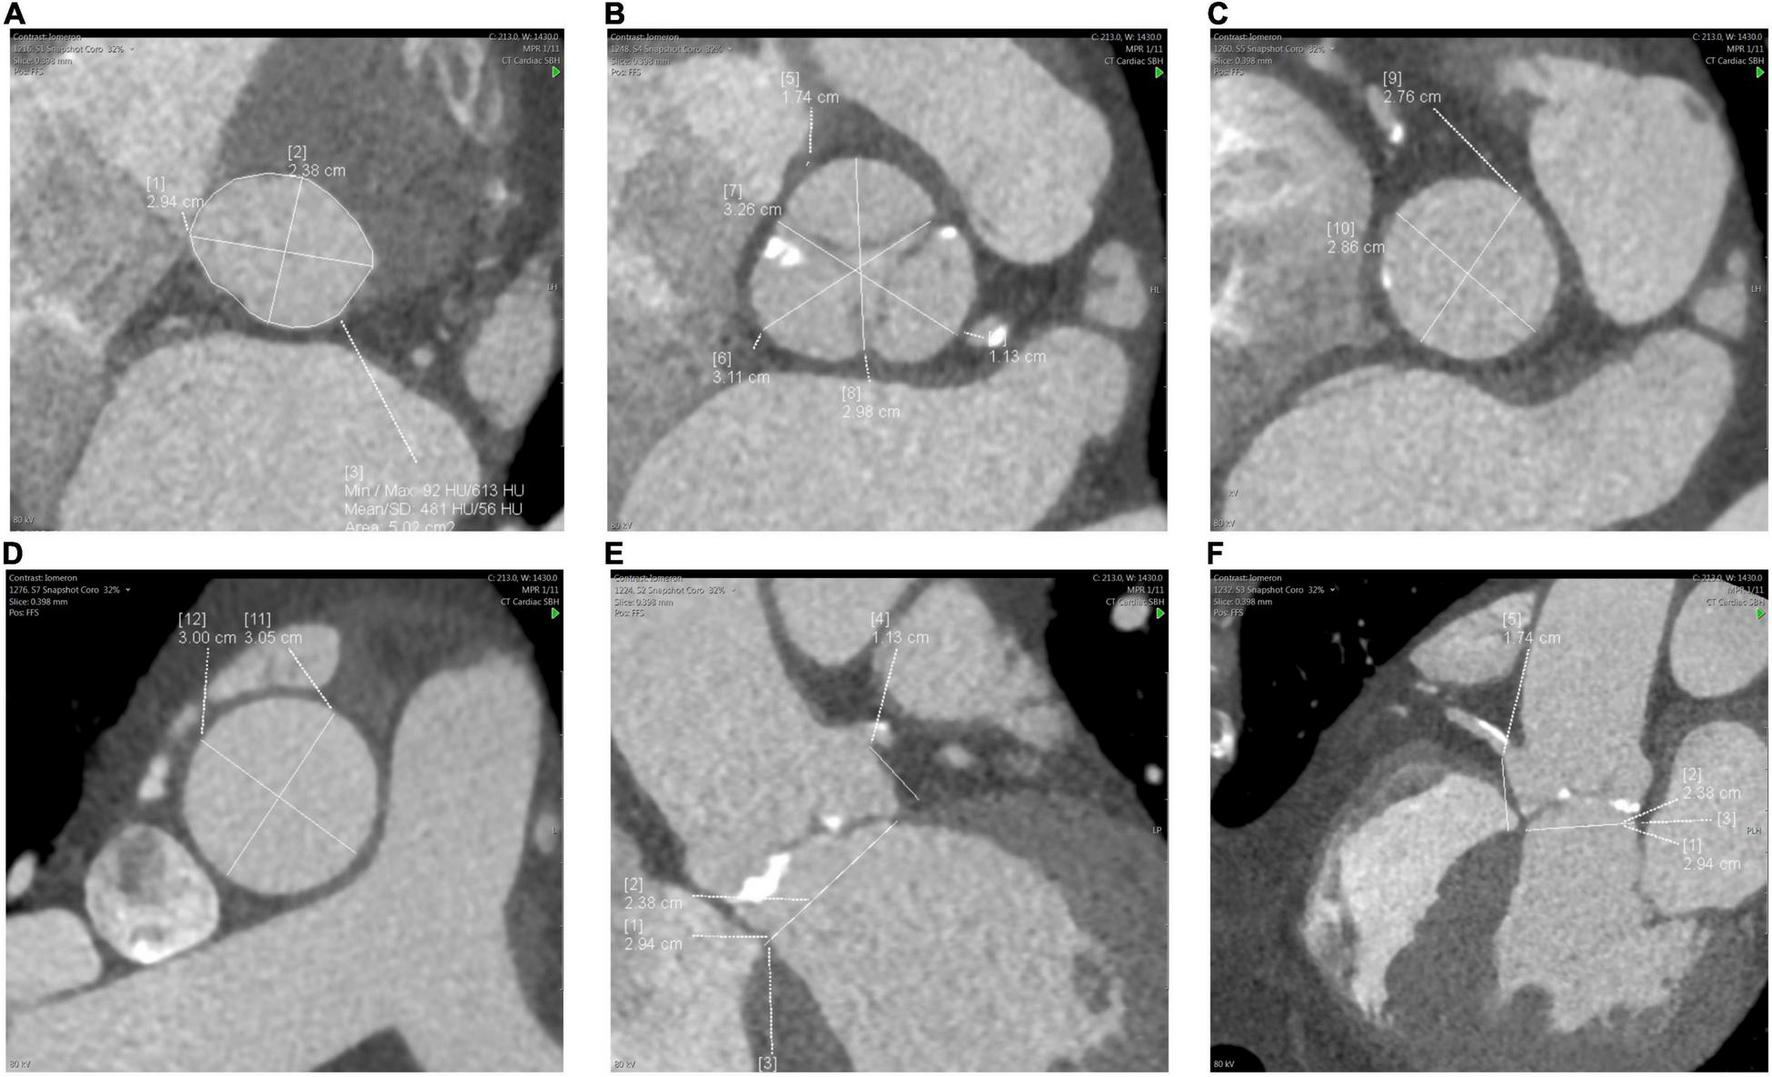

First, using multiplanar reconstructions (MPR), CT can be used to determine the optimum fluoroscopic projection for valve implantation-orthogonal to the aortic valve (29). This has been shown to reduce additional aortograms, procedural time and contrast use (33). Second, CT provides an accurate guide for sizing an aortic bioprosthesis based on aortic valve (AV) annular dimensions, with a resulting reduction in post-TAVR aortic regurgitation (34, 35). Annulus diameters, area and perimeter are typically used to derive the most appropriate transcatheter valve diameter, applying recommendations provided in manufacturers’ charts. Third, additional measurements are typically taken at levels of the sinus of Valsalva, sino-tubular junction, ascending aorta and the heights of the coronary ostia from the AV annulus- guiding the procedure and enabling the prediction of complications (Figure 2). Low coronary ostial heights and narrow sinuses of Valsalva are associated with a higher risk of coronary obstruction and difficulty in coronary artery engagement for angiography or intervention (36, 37). Correct valve sizing to prevent oversizing is essential to prevent annular rupture, which often results in fatal outcomes (38).

FIGURE 2

Measurements of the aortic root and ascending aorta. (A) aortic valve (AV) annulus, (B) sinus of Valsalva, (C) sino-tubular junction, (D) ascending aorta, (E) left coronary ostial height from AV annulus, (F) right coronary ostial height.